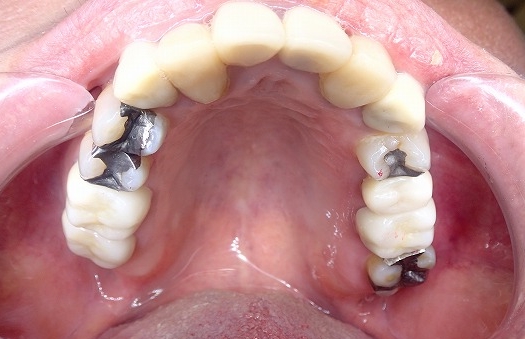

奥の銀歯の見え方

奥歯の金歯は、他人からは笑顔の時に

光って見えます。

反対側の銀歯はこうみえる